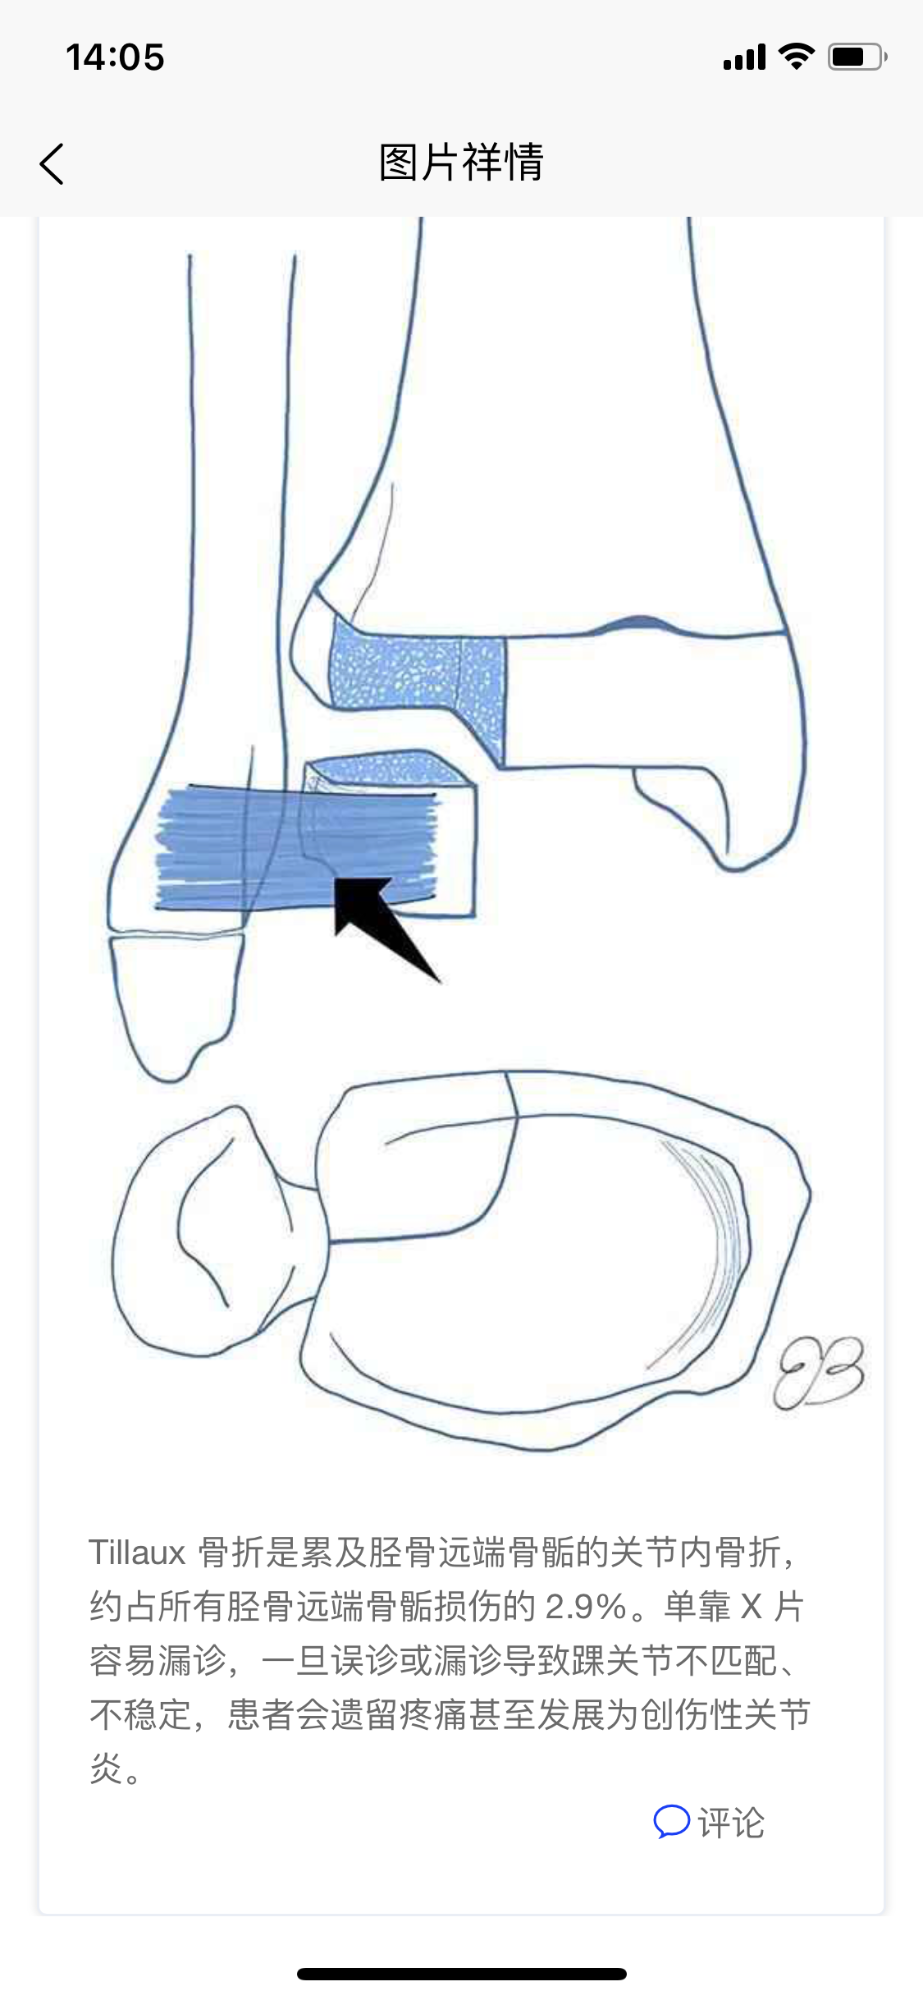

图片类主题祥情页面

此页显示图片类主题祥情,包括评论互动。